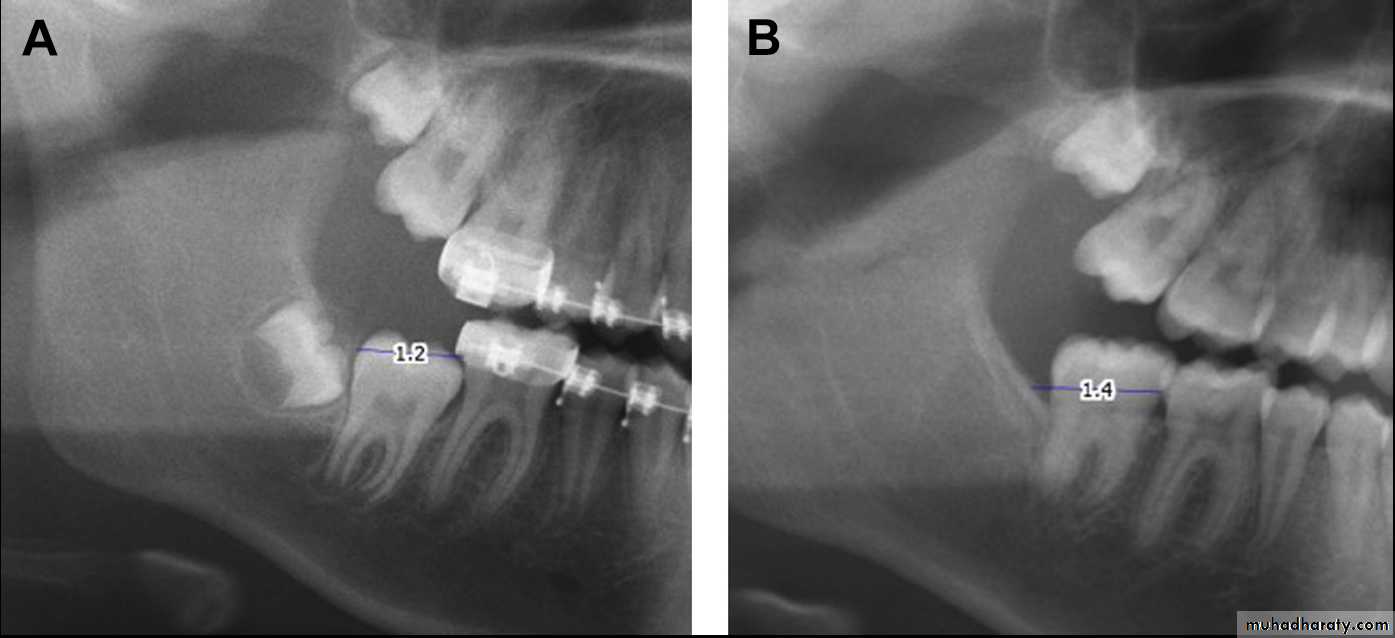

The procedure should ideally be performed when two-thirds of the second molar root is formed, which is usually between the ages of 11 and 14. If surgery is performed too soon then the tooth may be unstable and may shift in position. If performed too late then there is risk of root fracture and possible disruption of blood supply leading to pulpal necrosis.After adequate anesthesia, a mucoperiosteal flap is elevated distal to the first molar. Ostectomy is performed as necessary with a surgical drill to expose the second molar, and soft tissue around the crown is debrided. A dental elevator is used to apply distal and occlusal pressure to the tooth until the mesial marginal ridge of the second molar is at the same level as the distal marginal ridge of the adjacent first molar.

A, Posterior eruption space, measured from the distal contact point of the first molar to the most inferior point on the ascending ramus, on a preoperative image. B, Postoperative radiograph of the same patient.